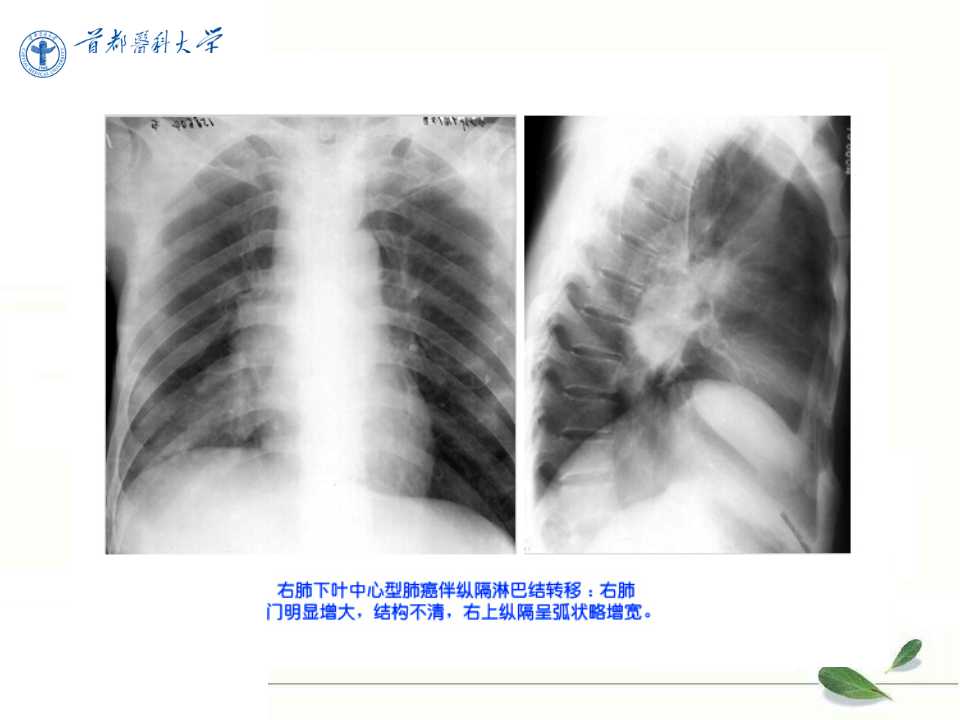

肺癌的影像学检查